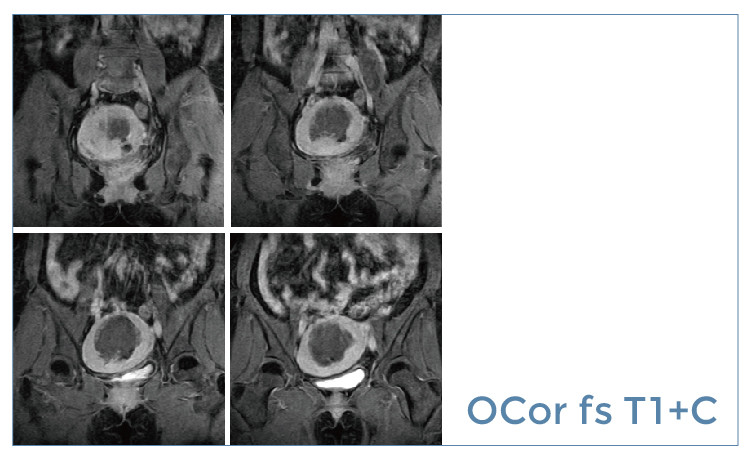

【朗润影像档案】20190621磁共振影像病例结果讨论